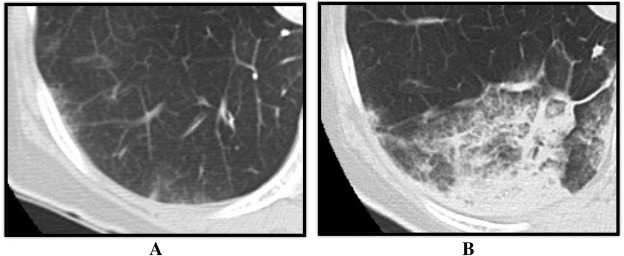

It has been hypothesized that exposure of high reperfusion pressure to the reperfused area after balloon dilation may lead to RPI [14] ;  [18], and Feinstein et al. have reported that RPI was frequently in the patients with > 35 mm Hg of mean PAP before BPA [13]. However, no previous study has assessed the relation between the local pressure and safety before and after BPA, and this study is the first documentation which clarifies the association between distal reperfusion pressure and the incidence of RPI (Fig. 4). In addition, we identified an optimal cut-off value (19.5 mm Hg) as a novel monitoring parameter to assure stable BPA result. We would like to suggest that combined strategy with IVUS for selecting an appropriate balloon size and a pressure wire for monitoring distal perfusion pressure would facilitate safe and effective BPA procedures, which will allow more aggressive BPA by increasing the target number of dilations in one session.

Both pulmonary artery right A2 and A3 were dilated by BPA. RPI was observed in ...

Fig. 4.

Both pulmonary artery right A2 and A3 were dilated by BPA. RPI was observed in pulmonary segment 2 where Pd changed from 10 to 28 mm Hg, but not observed in pulmonary segment 3 where Pd changed from 8 to 19 mmHg. BPA, balloon pulmonary angioplasty; Pd, mean pulmonary arterial distal to the stenosis; Pp, mean pulmonary arterial proximal to the stenosis; RPI, reperfusion pulmonary injury.